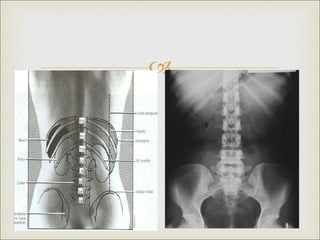

RADIOGRAFIA SIMPLE DE

ABDOMEN

RX SIMPLE DE

 Placa RUV

 Permite obtener una visión convencional de las

estructuras esqueléticas, intraabdominales y de las

vías urinarias

 Estudios sin medio de contraste y no invasivo

 sencillo

RX SIMPLE DE ABDOMEN   Placa RUV  Permite obtener una visión convencional de las estructuras esqueléticas, intraabdominales y de las vías urinarias  Estudios sin medio de contraste y no invasivo  sencillo

INDICACIONES   Detección de urolitiasis  Evaluar cuerpos extraños en al aparato urinario  Examinar posición o colocación de catéteres  Para diagnosticar íleos paralíticos u obstrucciones intestinales.